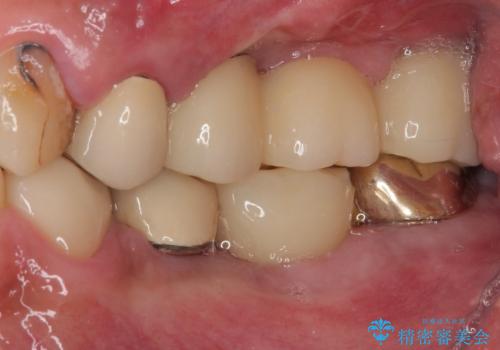

- 土台の歯が割れてしまって、歯がグラグラしているとのことで来院された患者様です。

いずれの歯も抜歯が必要な状態であり、抜歯即時埋入によるインプラント治療を行うこととしました。

右上奥歯は骨欠損の範囲が広いため、抜歯即時埋入は可能であっても、即日で仮歯を装着する即時荷重は難しいと判断されたため、手前の歯まで仮歯を装着することとしました。